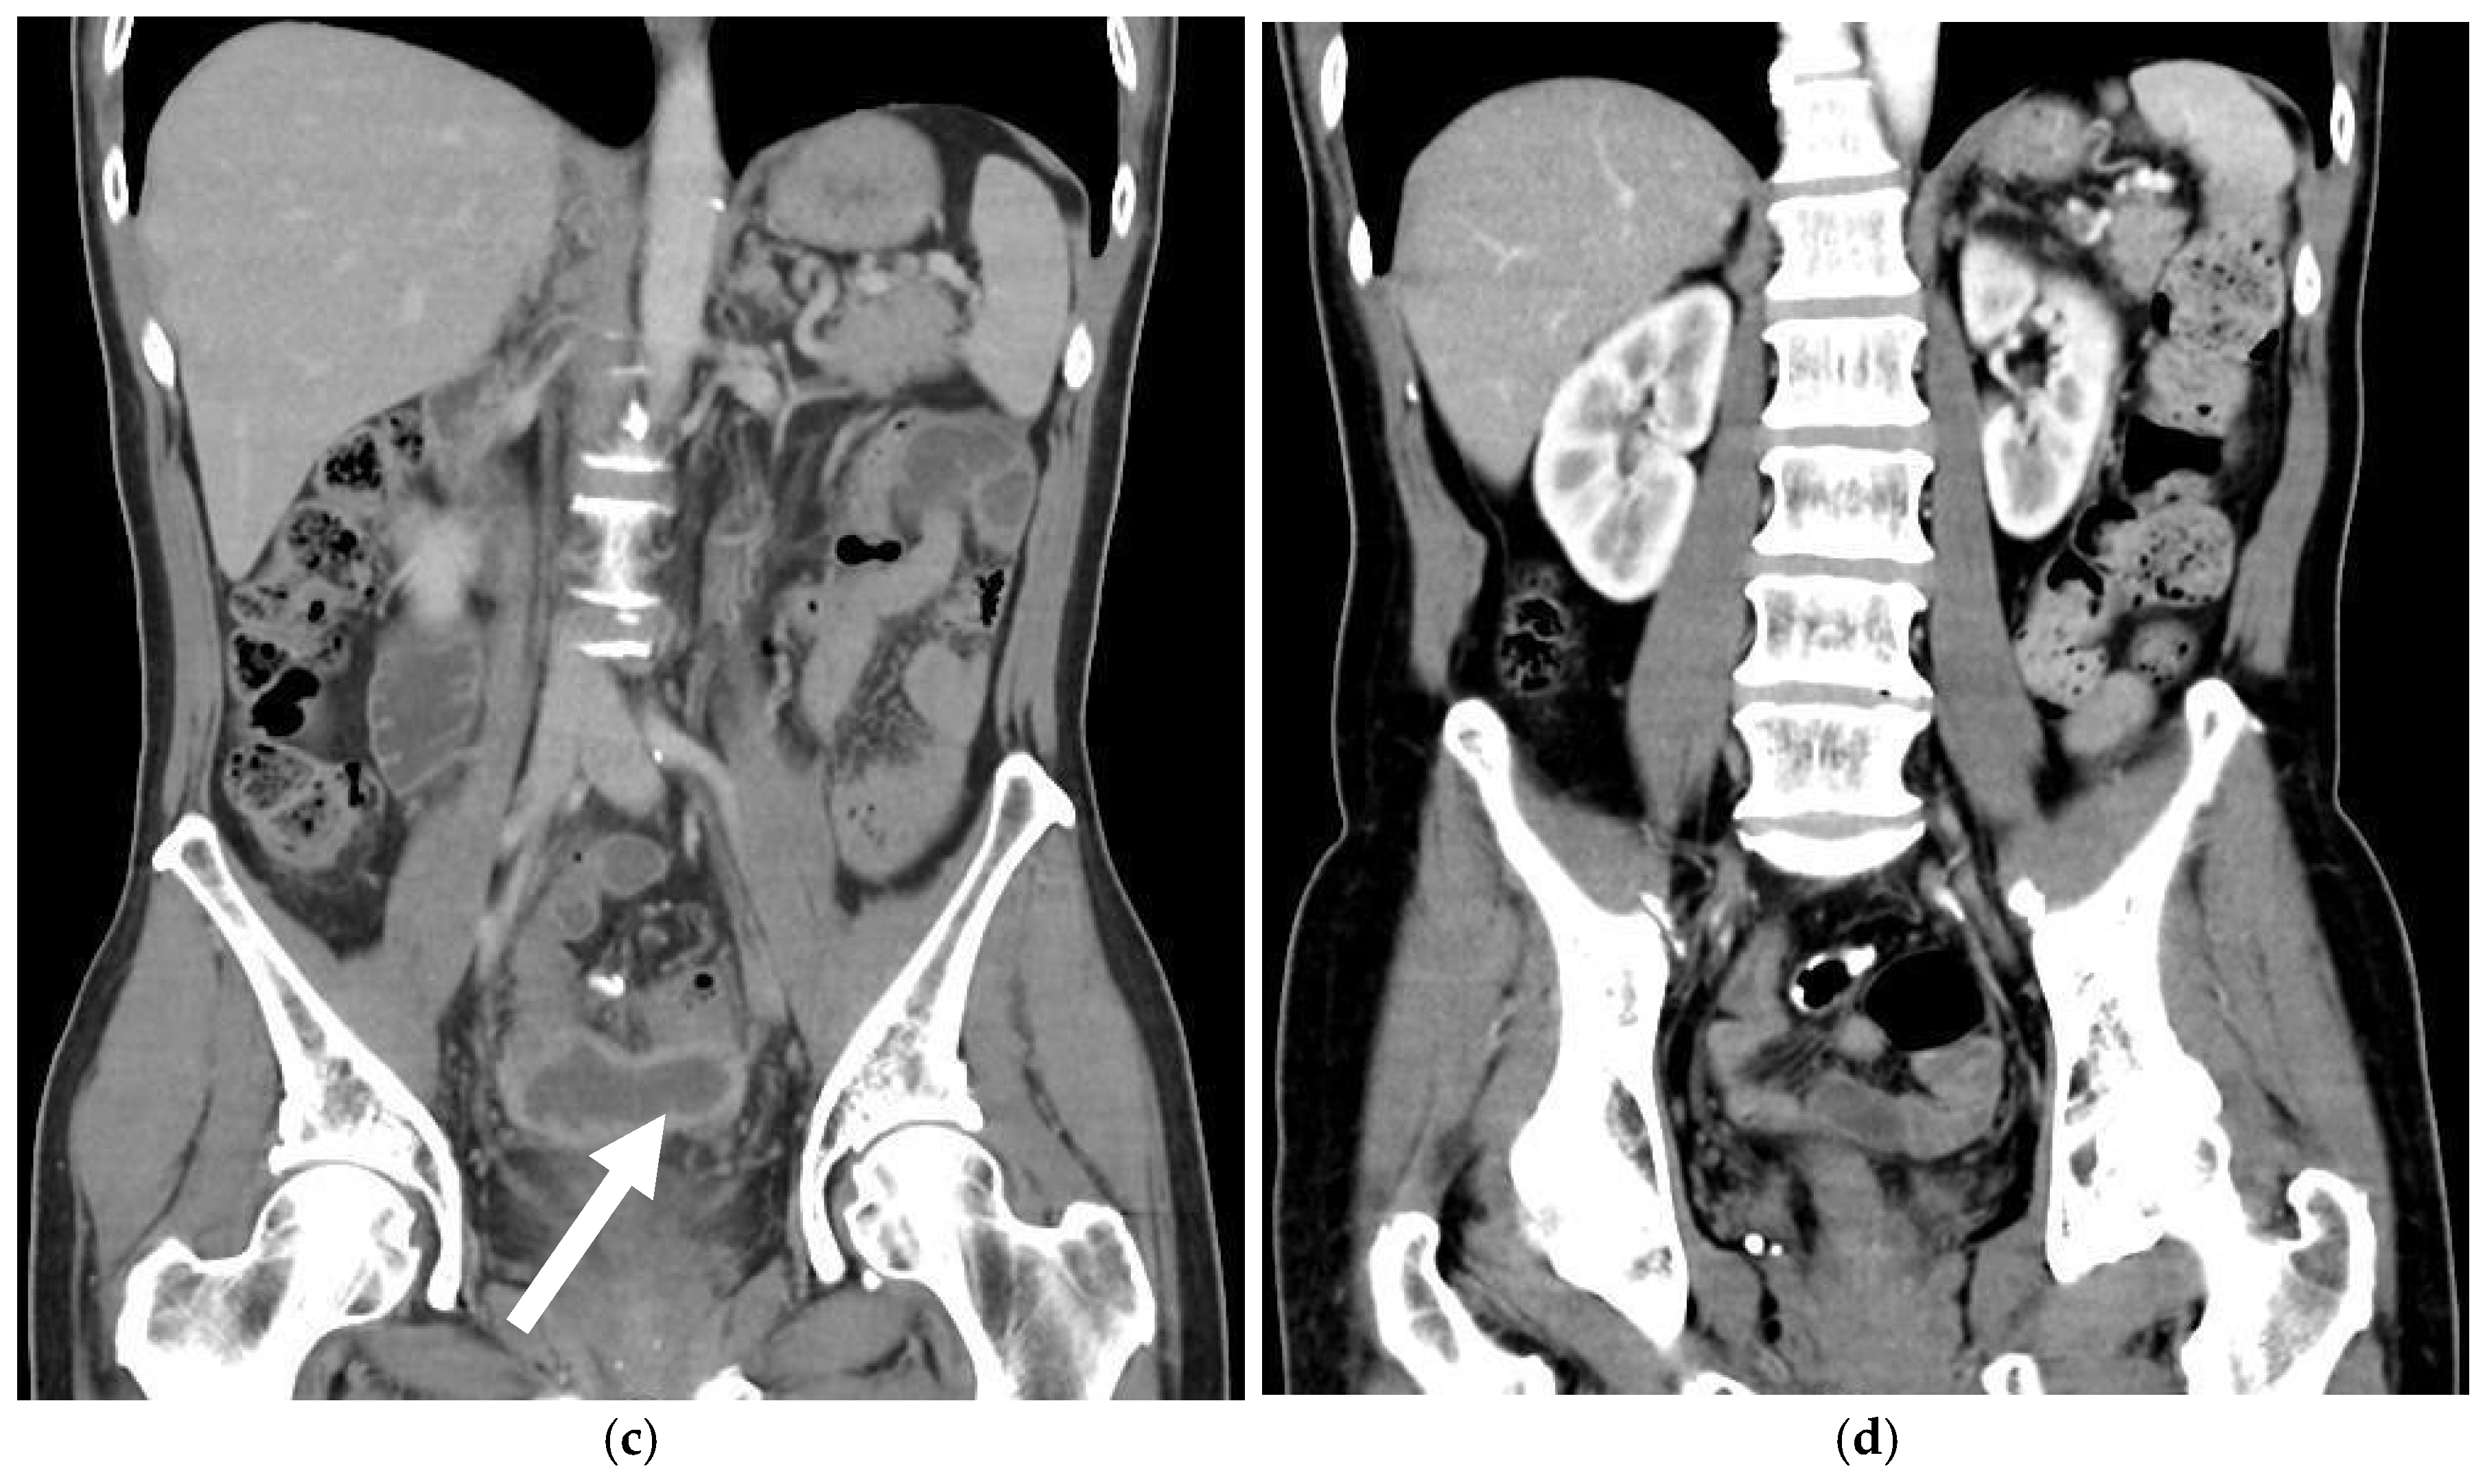

- Shimamura et al. (2015) described a case of neovaginal perforation complicated by an intra-abdominal abscess, where the clinical symptoms and radiologic findings were incongruent [18]. Surgical intraperitoneal drainage was performed due to concerns that the abscess might not resolve with antibiotics alone.

| Image findings | A large amount of fetid mucus in the abdominal cavity via laparoscopy |

| CT: a massive abscess occupying a significant portion of the intra-abdominal cavity |